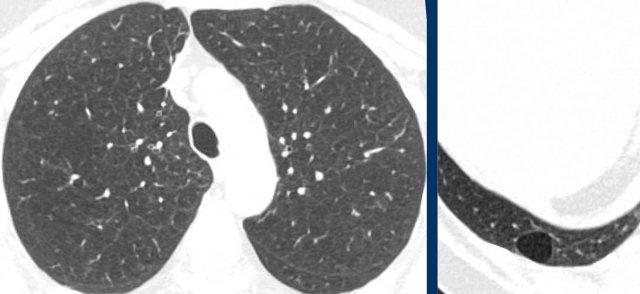

Các nang trong BHD có xu hướng phân bố ưu thế ở vùng phổi thấp và ngoại vi.

Đôi khi các nang có ranh giới được xác định bởi các vách liên tiểu thùy, tạo cho chúng hình dạng tam giác hoặc thấu kính đặc trưng (đầu mũi tên trong hình 2 và 4).

Các nang BHD không nhiều, thường ít hơn 50 nang. Đôi khi số lượng nang rất ít với hình ảnh rất tinh tế (hình 3), nhưng không được bỏ sót.

Hình ảnh

- Các nang BHD. Một số nang tiếp giáp với màng phổi (mũi tên vàng) hoặc các rãnh liên thùy. Các nang ở vùng phổi thấp cũng có thể gặp trong LIP. Khí phế thũng cạnh vách liên tiểu thùy có phân bố ưu thế ở vùng phổi trên.

- Phân bố ưu thế ở vùng phổi thấp và các nang hình tam giác (đầu mũi tên) trong BHD.

- Lưu ý hình ảnh rất tinh tế với phân bố ưu thế ở vùng phổi thấp.

- Các nang BHD điển hình

Đây là hình ảnh của một phụ nữ 56 tuổi, có tiền sử tràn khí màng phổi tái phát và hiện tại nhập viện lần này cũng vì tràn khí màng phổi (mũi tên).

Nhận xét hình ảnh

Có nhiều nang thành mỏng – hơn bốn nang. Lưu ý vị trí phân bố gần các rãnh liên thùy và ở ngoại vi phổi.

Kết luận

Đây là trường hợp hội chứng Birt-Hogg-Dubé (BHD).

Hai bệnh phổi dạng nang thường biểu hiện bằng tràn khí màng phổi là LAM và BHD.

LAM biểu hiện là các nang đơn thuần, thành mỏng, hình tròn hoặc bầu dục, đều đặn với phân bố lan tỏa.

Vị trí ngoại vi và cạnh rãnh liên thùy của các nang BHD thường tạo ra các góc nhọn, khiến chúng có hình dạng thấu kính.

Khi các nang có hình ảnh đặc trưng này, chúng có độ đặc hiệu cực kỳ cao cho chẩn đoán hội chứng Birt-Hogg-Dubé.